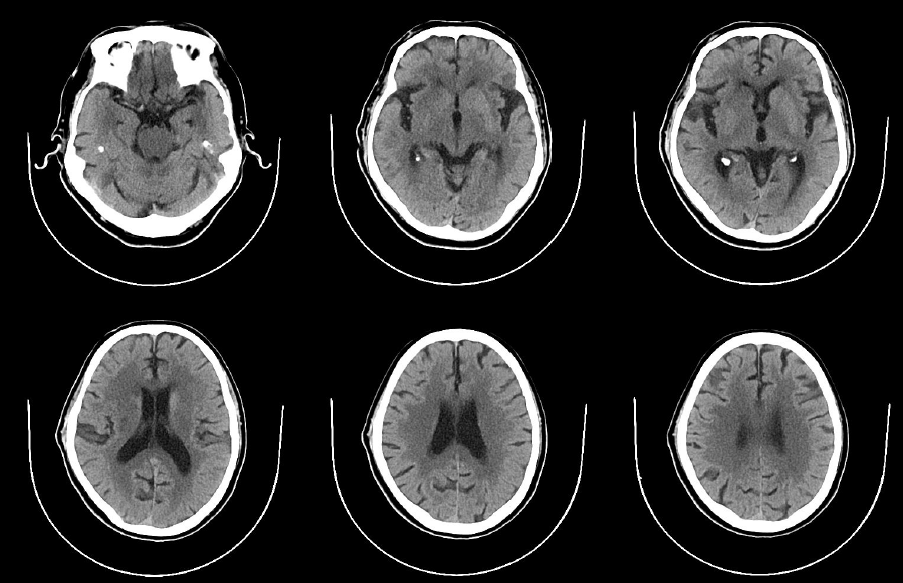

急诊头颅CT

病历夹什么径技·第152期|串联营病历夹:川陕大营_https://www.jmylbn.com_新闻资讯_第8张

术后即刻、14小时与18小时复查头颅CT

病历夹什么径技·第152期|串联营病历夹:川陕大营_https://www.jmylbn.com_新闻资讯_第29张

病历夹什么径技·第152期|串联营病历夹:川陕大营_https://www.jmylbn.com_新闻资讯_第30张

病历夹什么径技·第152期|串联营病历夹:川陕大营_https://www.jmylbn.com_新闻资讯_第31张

病历夹什么径技·第152期|串联营病历夹:川陕大营_https://www.jmylbn.com_新闻资讯_第32张

<<滑动查看下一张图片>>